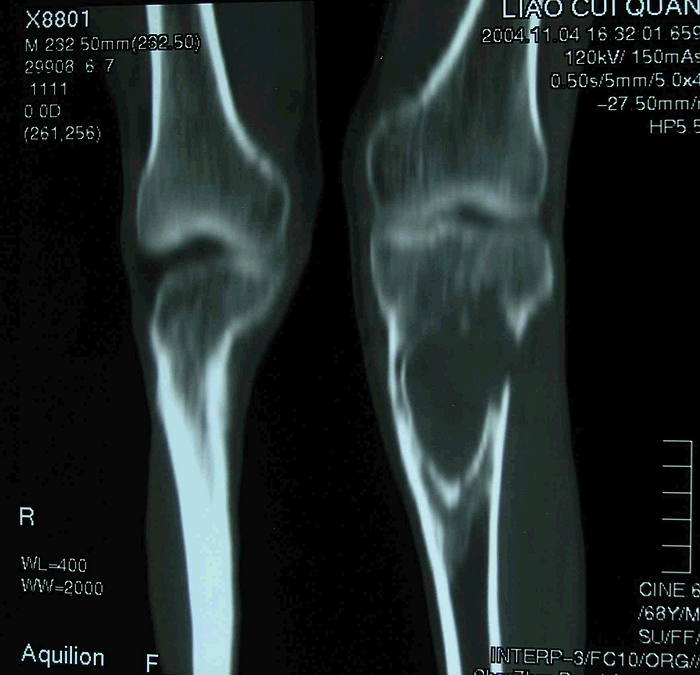

5、病例5:男 65岁 左胫骨上段毛细血管扩张性骨肉瘤,因活检术后持续性出血,行大腿中段截肢术

图 29 术前CT冠状面象